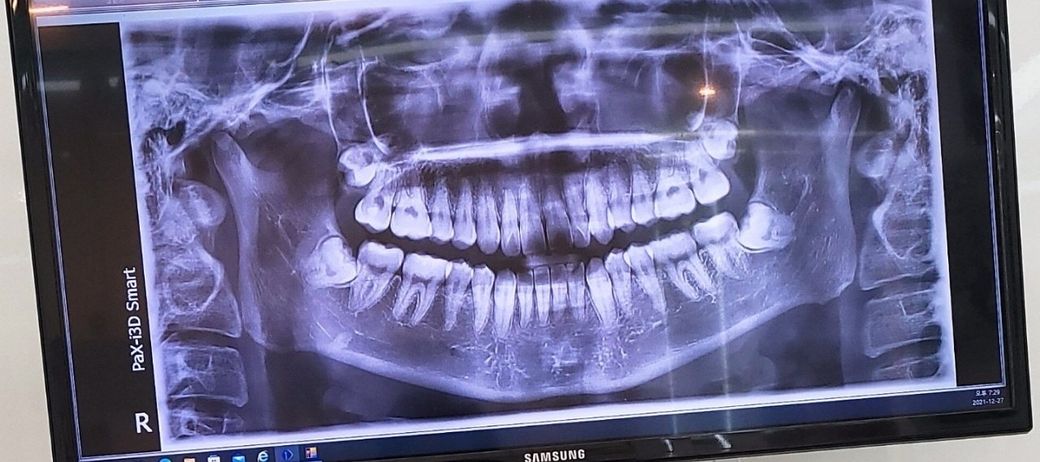

사랑니를 발치 해야 할까요 어떻게 해야될까요?

사진을 찍었는데 치과마다 말이틀려서 여쭤봅니다 ㅠ

그냥 놔둬도 별 문제 없다고 하는 곳도 있고 권유는 안하지만 원하면 발치하라는곳도 있어요. 어떻게 해야 할까요? 이대로 냅둬도 괜찮을까요?

사진상으로 보아서는 사랑니를 발치하는 것이 좋습니다.

현재 질문자님은 치아가 부분 매복되어 있습니다. 부분 매복되어 있거나 완전 매복되어 있어 앞쪽 어금니 사이에 음식물이 끼어 충치가 발생하거나 염증이 발생하게 되면 반드시 빼는 것이 좋습니다.

모두 맞는 말입니다. 모든 사랑니를 다 발치 하는건 아닙니다. 똑바로 나서 관리가 잘되거나 뼈속에 뭍혀져 있으면 발치 안하셔도 무방합니다. 사진상으로 보니 사랑니 4개 모두 뼈속에 뭍혀 있는 상태이신거 같습니다. 지금 당장은 발치 안하셔도 되지만 추후에 염증이 생긴다거나 불편하시면 그때는 발치 하시는걸 추천드립니다.

현재 아래쪽 사랑니의 경우 누워서 나오고 있기에 하악 제2대구치에 문제를 일으키기 전에 예방적으로 발치하시는게 좋아보이며 동시에 상악의 사랑니도 발치하는게 좋겠습니다.

아래 사랑니는 수평 매복지치로 그대로 두는 경우 앞에 어금니가 손상을 받을 수 있기에 발치를 권장드리며 위에 사랑니는 너무 깊이 묻혀 있어 특별한 불편감이 없는 경우 조금 더 지켜보길 권고드립니다.